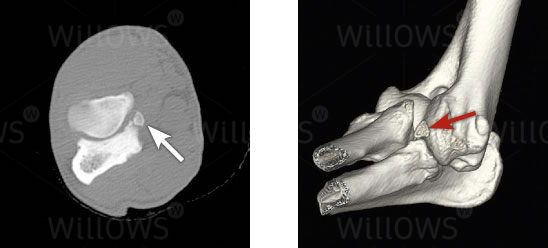

Fig 1: CT scans showing a fragment of bone in the elbow joint (arrows)